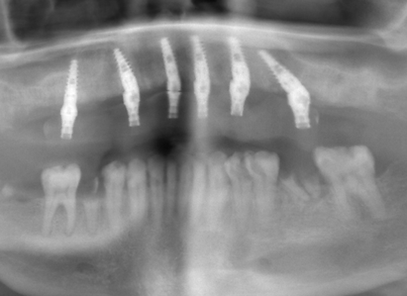

A dental implant post is a titanium screw placed in the jaw bone which anchors an implant crown. Generally, the post is then given 2-3 months of healing under the gums before the implant crown is connected.

$49 3D X-ray

With our technology the implant post can even be placed same-day as your first visit

TEETH IN A DAY DENTAL IMPLANTS